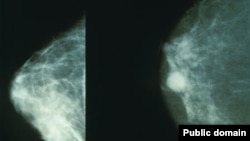

افغانستان کې د سینې سرطان زیاتوالی؛ افغانان د ځانګړو مرکزونو او روغتیايي خدمتونو له نشتوالي شکایت کوي

ارشیف: په دې تصویر کې د سرطان ناروغۍ نښې نښانې لیدل کېږي.

د کابل په جمهوريت روغتون کې د ملي انکولوژي څانګې مسوولان که څه هم مشخصې شمېرې نه ورکوي، خو سږ کال په افغانستان کې د تي یا سینې سرطان د زیاتوالي خبر ورکوي.

په کابل کې د جمهوريت روغتون د انکولوژي څانګې ته لسګونه مېرمنې د تي یا سینې سرطان د درملنې لپاره ورځي.

په همدې حال کې د کابل د جمهوریت روغتون د انکولوژي د ملي څانګې مسوولان که څه هم مشخصې شمېرې نه وړاندې کوي، خو په روان کال کې په افغانستان کې د سینې سرطان د زیاتوالي خبر ورکوي.

د سرطان د مخنیوي د ملي پروګرام مرستیال ډاکتر خالد خلیلزي ازادي راډیو ته وویل: "د سینې سرطان یو له هغو عامو سرطانونو څخه دی چې د افغانستان په ګډون په ټوله نړۍ کې مخ په ډېرېدو دی. د انکولوژۍ په ملي روغتون کې دې ناروغۍ د تېر کال په پرتله زیاتوالی موندلی، خو له نېکه مرغه چې دا سرطان که په لومړیو پړاوونو کې تشخیص شي د درملنې او مخنیوي وړ دی. د سینې د سرطان ځینې لاملونه شته لکه د دوو کلونو لپاره ماشوم ته د شیدو نه ورکول، د امیندوارۍ د مخنیوي درملو کارول، ډېر وزن او د هورمونونو بدلونونه، دا ټول هغه عوامل دي چې مخنیوی یې کېدی شي."

هڅه وشوه چې په دې اړه د طالبانو حکومت د عامې روغتیا وزارت نظر هم واخیستل شي، خو د دغه وزارت ویاند شرافت زمان د ازادي راډیو پوښتنو ته ځواب ونه وایه، خو په ۱۴۰۲ کال کې یې له سیمه‌ییزو رسنیو سره په خبرو کې په افغانستان کې د سینې سرطان د ۶۲۴۰ ناروغانو د ثبت خبر ورکړی و او ویلي یې وو چې دا د سرطان ناروغانو ۲۶ سلنه جوړوي.

په ورته وخت کې د هرات د حوزوي روغتون د انکولوژي څانګې مسوولانو هم ازادي راډيو ته وویل چې سږ کال دوی ته د سینې د سرطان نږدې ۴۱ ناروغان ورغلي دي.

د روغتیا نړیوال سازمان د معلوماتو له مخې، هر کال شاوخوا ۲۰زره افغانان د سرطان په بېلابېلو ډولونو اخته کېږي چې له دې ډلې تر ۱۵زره زیات یې د دغې ناروغۍ له امله مري چې تر ټولو عام ډول یې د سینې، معدې، مري، شونډې، خولې، رحم او سږي سرطانونه دي.